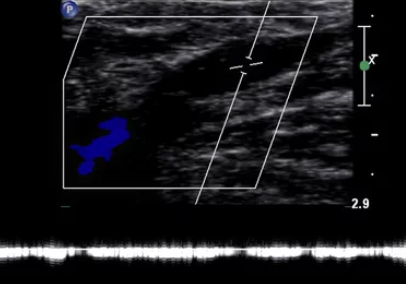

혈관외과 전문의가 있는 곳, 초음파 장비가 좋은 곳일수록

✔ 정밀 초음파 검사비

약 5만~10만 원 전후.

혈관 상태에 따라 진단비가 달라지기도 해요.

안전하게 치료하려면 정확한 초음파 진단이 필수입니다.